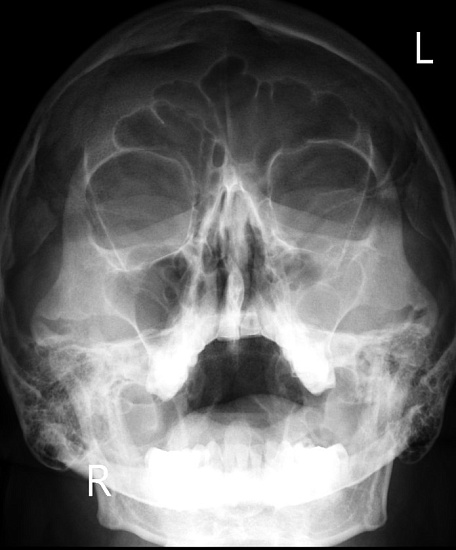

Рентгенография придаточных пазух носа – важный метод обзорного исследования состояния придаточных пазух носа.

Диагностическая услуга выполняется в одной проекции.

• подозрение на наличие патологии придаточных пазух носа: заложенность носа, головные боли, зеленое отделяемое, частые рецидивирующие воспалительные заболевания пазух;

• для исключения в пазухах острого или хронического воспалительного процесса, наличия кист, полипов, оценки развития системы придаточных синусов носа;

• рентгенография также позволяет оценить положение носовой перегородки.